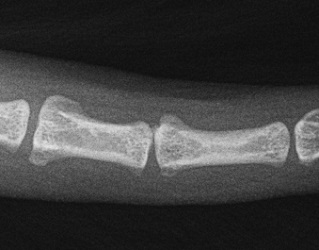

Patella

04.06.2024

re-0, li-1